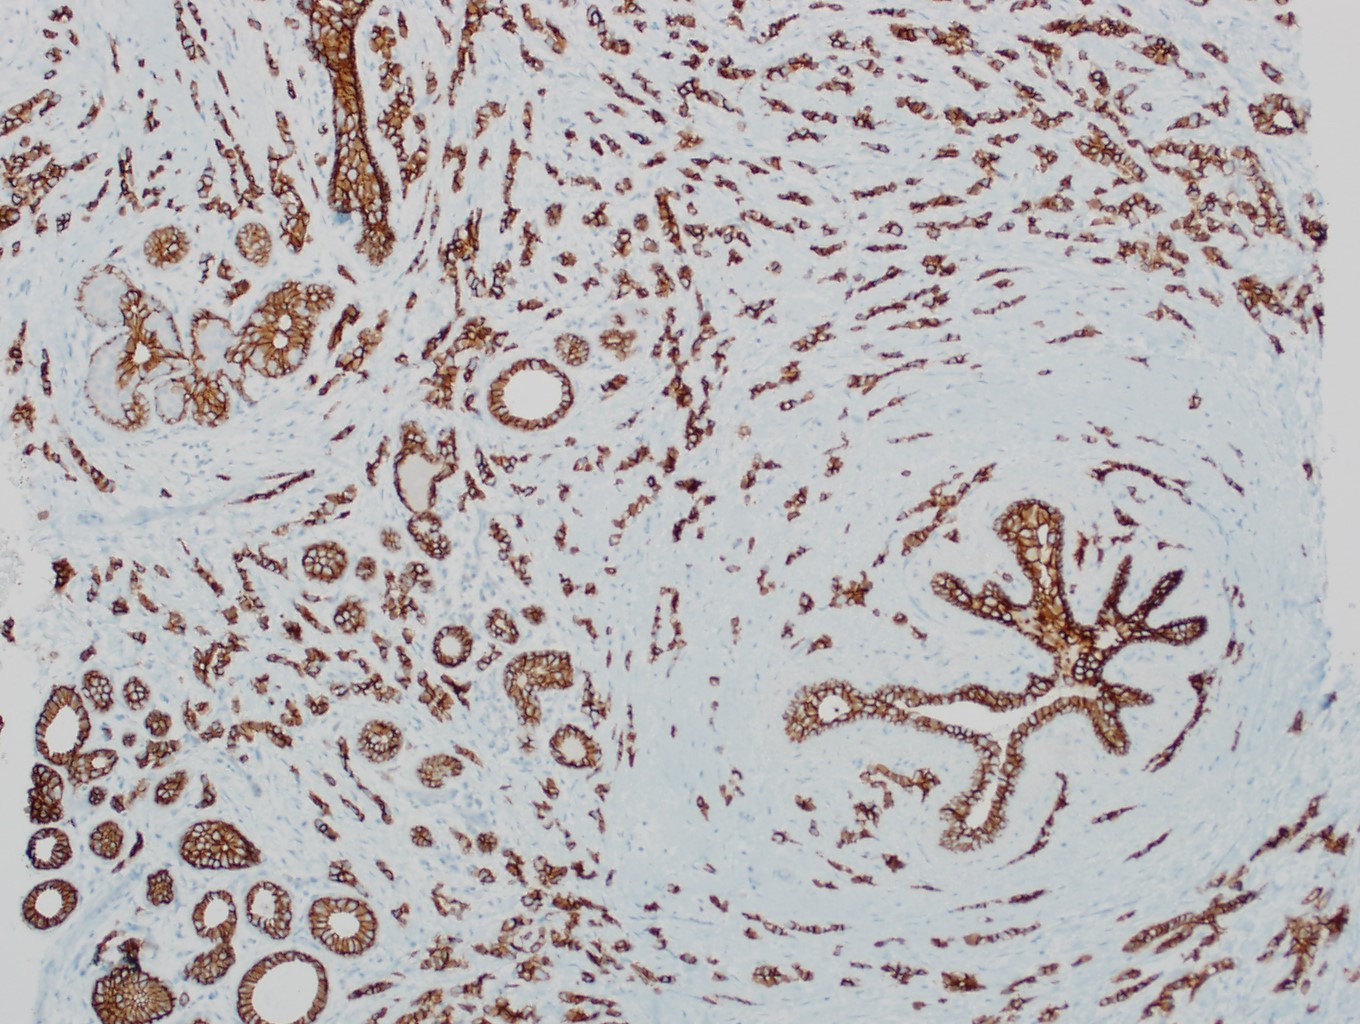

Microscopic (histologic) images

Contributed by Julie M. Jorns, M.D., Kristen E. Muller, D.O., Gary Tozbikian, M.D. and Emad Rakha, M.D.

Positive stains

- Luminal low molecular weight cytokeratins (CK8 / 18, CK19 and CK7 and pancytokeratins such as AE1 / AE3, CAM 5.2, MNF-116), EMA, E-cadherin, p120, ER (60 - 80%), PR (50 - 70%), HER2 (15 - 20%) (Am J Clin Pathol 2006;125:377)

- No myoepithelial cell lining (as seen in DCIS or benign lesions)

- Endothelial lining is present and is CD31+, ERG, D2-40+, CD34+ and factor VIII+